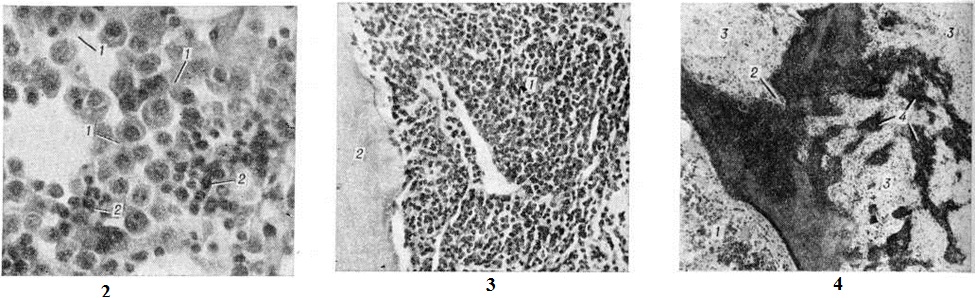

Электронная микроскопия плазматических клеток при Миеломная болезнь позволяет выявить гипертрофию протеин-синтезирующих структур — шероховатую эндоплазматическую сеть в виде мешков и цистерн, оттесняющих ядро к периферии, полирибосомы и развитой комплекс Гольджи. Ацидофильные тельца выявляются в виде оптически плотных гранул, содержащих аморфную белковую субстанцию. Полагают, что они состоят из конденсированного парапротеина. В связи с высоким содержанием белка и рибонуклеопротеидов цитоплазма этих клеток резко пиронинофильна, имеет ШИК-положительную реакцию, люминесцирует при окраске тиофлавином Т. Наряду со зрелыми плазмоцитами выявляются плазмобласты, атипичные гигантские одно и многоядерные клетки. Клеточный состав разрастаний варьирует в различных случаях и нередко отличается в разных участках скелета. Разрастания плазматических клеток могут быть узловатыми, диффузными или диффузноузловатыми. Первый вариант, как показывают результаты трепанобиопсии, встречается главным образом в ранние стадии болезни. При этом на фоне нормального костного мозга выявляются множественные, довольно больших размеров (от 200 микрометров и более) очаговые разрастания плазматических клеток (рисунок 2), проникающие в прилежащую ткань. Прогрессирование Миеломная болезнь характеризуется развитием диффузной инфильтрации костного мозга плазматическими клетками (рисунок 3). Нередко это сопровождается развитием обширных узловатых разрастаний (цветной таблица, ст. 33, рисунок 8 и 9). Число клеток нормального гемопоэза заметно снижено. Могут выявляться поля миелофиброза, жировых клеток. Характерно значительное истончение костных пластинок вплоть до полного их исчезновения на больших участках, расширение каналов остеонов (гаверсовых каналов), частичное разрушение коркового вещества с прорастанием плазматических клеток в надкостницу. Рассасывание костной ткани протекает по типу гладкой, пазушной и остеокластической резорбции. Полагают, что остеопороз обусловлен нарушением процессов костеобразования вследствие повышенной секреции в костном мозге фактора, стимулирующего остеокласты. Репаративные процессы резко снижены, однако в ряде случаев наблюдается очаговое образование кости примитивного строения, преимущественно в области микро-переломов и в зонах кровоизлияний по периферии узловатых разрастаний (рисунок 4). Изредка рассасывание костной ткани отсутствует, имеет место утолщение костных пластинок.